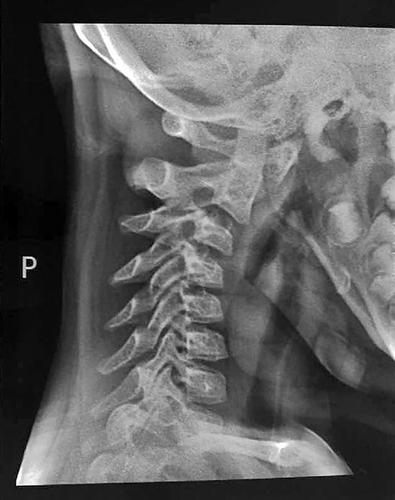

经过拍片检查,盈盈的颈椎第一、二、三椎向前错位。

“当时那个女孩的头颈向一侧扭转,稍微活动头部就直喊疼?!庇σ缴?,经过拍片检查,盈盈的颈椎第一、二、三椎向前错位,“这么严重的颈椎病发生在这么小的孩子身上,这是我从医30多年来头一回碰到。”